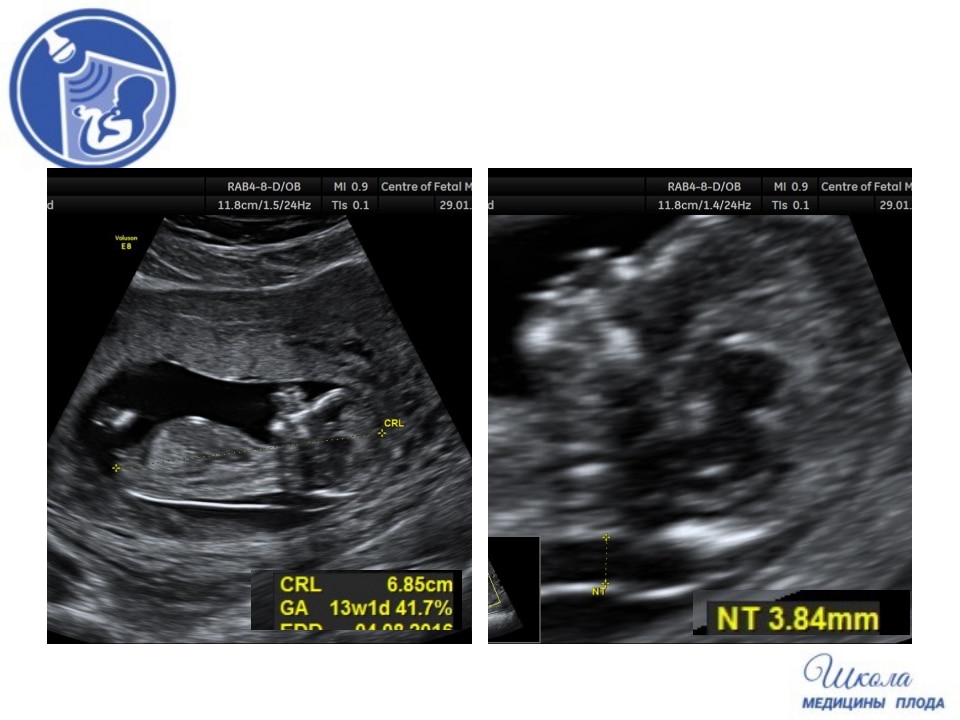

Вопрос 7

Пациентка пришла на УЗИ при сроке 13 недель 2 дня. Проанализируйте изображения и клип сердца и дайте свое заключение